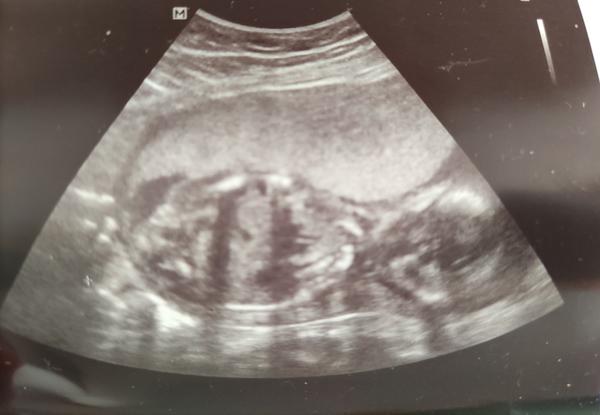

Fotky z ultrazvuku ve 20. týdnu těhotenství

Ahoj holky, prosím o radu. Dostala jsem tyto fotky z ultrazvuku ve 20.tt. Konzultace s lékařem už není možná, protože mi je přeposílal. Máte někdo podobné a dokázaly byste popsat, co vidíte příp. jestli jde určit pohlaví? Moc děkuji za Vaše názory 🙂

Ale co mi pohlaví ukazovali tak to vaše vypadá také na holčičku 🙂 akorát mě ukazovali pohlaví zespodu :/

To mě taky doktor ukazoval zespodu, ale jednou říkal, že to vypadá na chlapečka a pak na holčičku. Chtěla jsem si fotky prostudovat doma, ale netušila jsem, že mi pošle tyhle, kde pořádně není nic vidět 😢

mě utz teprve čeká, ale upřímně z tvých fotek bych pohlaví vážně nepoznala 🙂